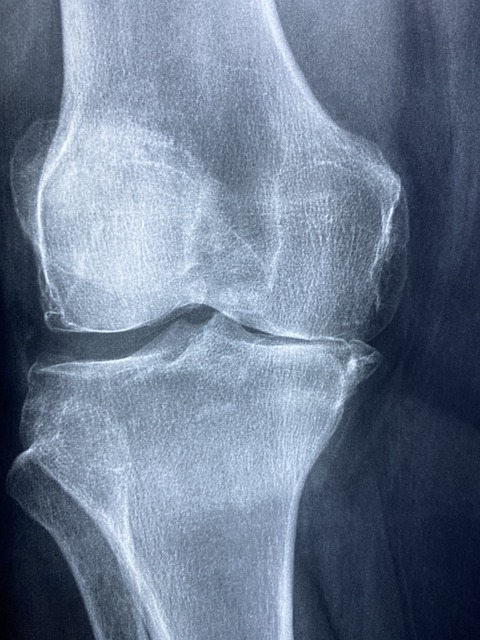

관절건강 질환을 진단하기 위해 신체 검사, X-ray, MRI, 관절경 검사 등이 사용됩니다. 이를 통해 관절의 상태를 정확히 파악하고, 적절한 치료 방안을 마련할 수 있습니다.